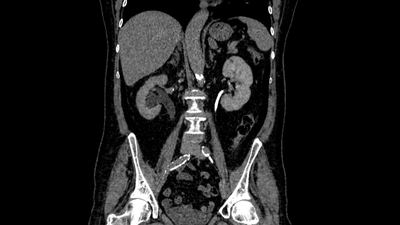

Наиболее информативное КТ с контрастированием: показывает степень расширения, уровень обструкции, функцию почек.